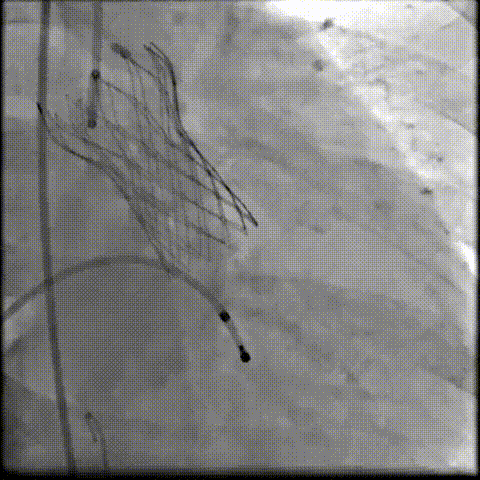

术中影像

根部造影可见返流;20mm球囊预扩,LCA灌注缝隙狭小

预置LCA保护;第一次释放,

团状钙化挤压导致瓣膜(AV23)少量下滑

回收后重新定位,第二次释放,

瓣膜(AV23)深度仍未达到最佳预期

完全回收,第三次定位释放,瓣膜(AV23)位置良好

瓣膜工作位释放“烟囱支架”;

瓣膜(AV23)完全释放后,“烟囱支架”后扩

最终造影,“烟囱支架”显影清晰,瓣膜形态及LCA灌注良好